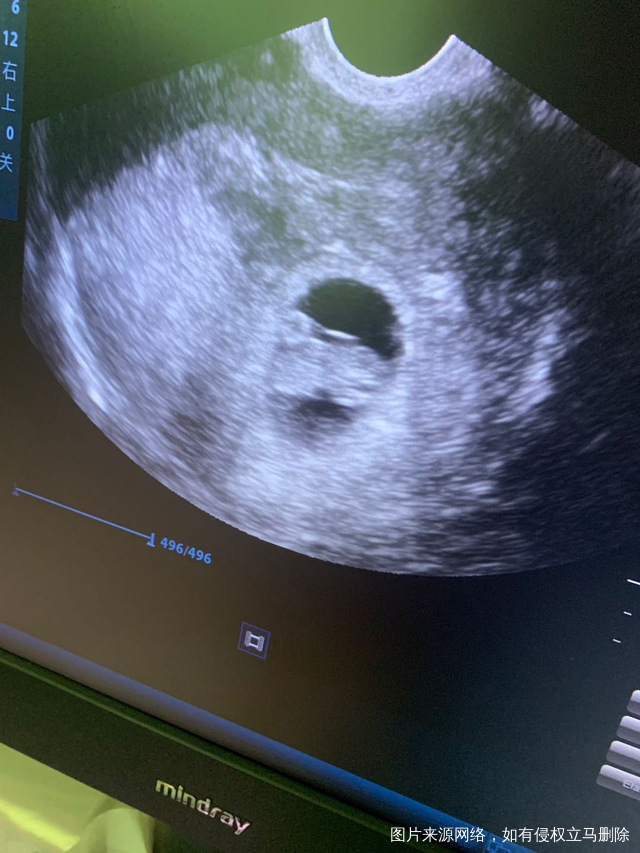

这张照片正常的吗图品中有没有宫腔积液或者盆腔

这张照片正常的吗?图品中有没有宫腔积液或者盆腔积液啥的?